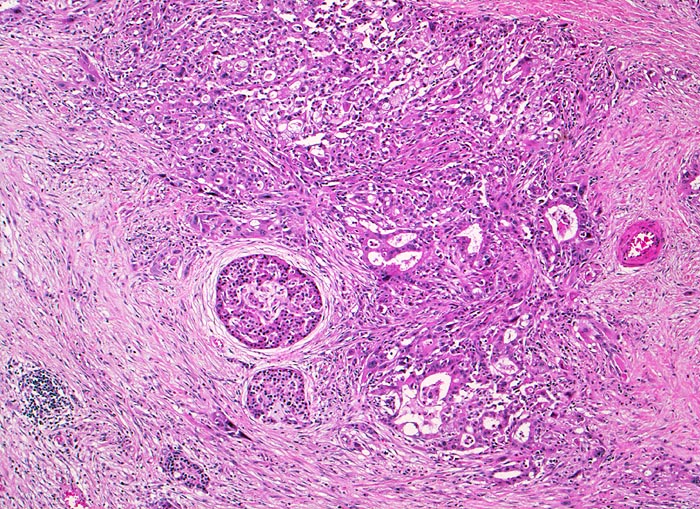

duktales Adenokarzinom des Pankreas

Kleindrüsiges Tumorinfiltrat. Angrenzend an das Tumorinfiltrat ausgeprägte Fibrose (harter Tumor!) mit lockerem Entzündungsinfiltrat und einzelne erhaltene Pankreasinseln.

Unscharf begrenzter weisser derber Herd im Pankreaskopfbereich. Stenosierung und praestenotische Dilatation von Ductus choledochus und Pankreasgang vor der Papille.

Zunehmender schmerzloser Ikterus. Sonographische Darstellung einer 4cm grossen echoarmen Raumforderung im Pankreaskopfbereich. Dilatation des Pankreasganges und des Ductus choledochus. Whipple Operation.